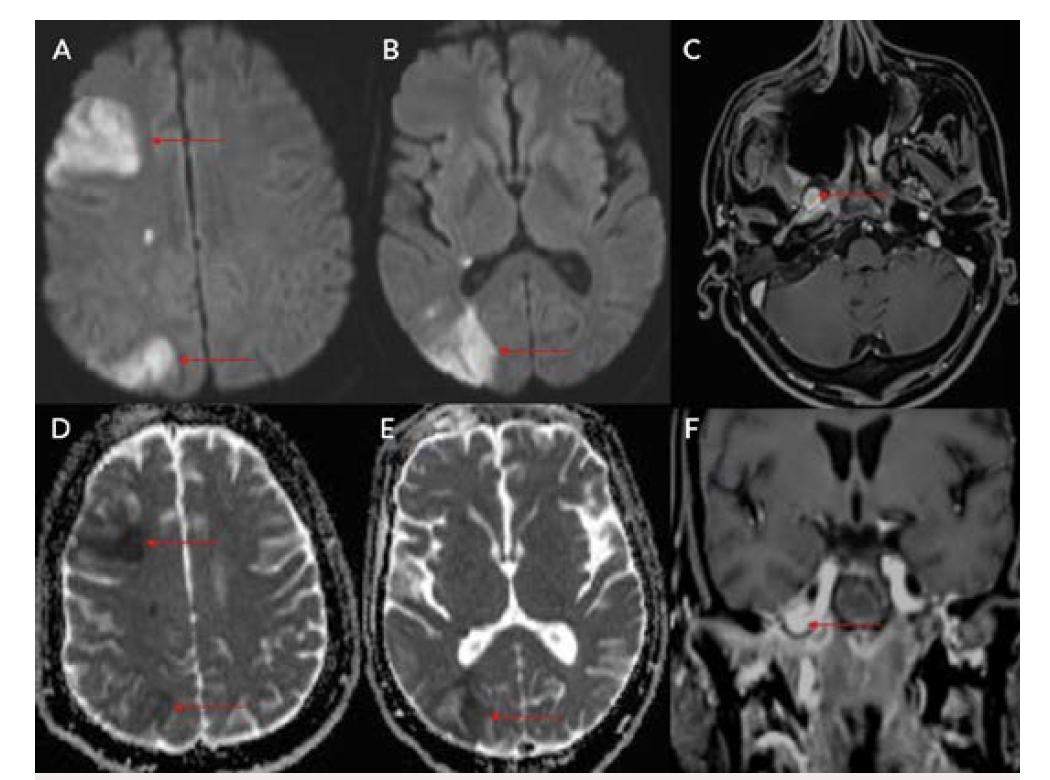

Eight patients were included during this study period; all were men between ages 34 and 61 (Table 1). Positivity to COVID-19 RTPCR test was detected over a period of 2 to 6 months prior to the acute hemorrhage. Six patients presented with massive hemoptysis; 2 presented with severe epistaxis. A contrast-enhanced computed tomography angiography was done in all patients. All 6 patients who presented with massive hemoptysis were detected to have pulmonary arterial pseudoaneurysms with associated cavitary lesions in the lungs (Figure 2). Among the 2 patients who presented with nasal bleed, 1 had a biopsy and culture-proven invasive fungal sinusitis with an internal maxillary artery pseudoaneurysm, probably of mycotic etiology. The second patient also diagnosed with invasive fungal sinusitis had multiple sinonasal debridements outside before presenting with massive epistaxis wherein a diagnosis of internal carotid artery pseudoaneurysm was made, probably secondary to iatrogenic or mycotic etiology. The presence of concomitant COVID-19 infection in these patients predisposed them to impairment of cell-mediated immunity, immune dysregulation, and a decrease in CD4 and CD8 counts, increasing their vulnerability to fungal infections. In 6 patients it was possible to obtain samples for fungal elements through biopsy. Endovascular embolization was performed under local anesthesia in 7 patients, and under general anesthesia in 1 patient. Different embolic agents were used: coils (Figures 3A and 3B), Amplatzer vascular plug (Abbott) (Figures 4A and 4B, Figures 5A and 5B), and glue (Figures 6A and 6B). However, 2 patients underwent lobectomy for extensive parenchymal disease apart from pseudoaneurysm. One patient with pulmonary artery pseudoaneurysm had contrast extravasation into the cavity during the procedure. All patients had cessation of hemorrhage. However, 2 patients required pulmonary lobectomy because of extensive parenchymal disease after embolization for the pseudoaneurysm.

COVID-19 infection has affected people worldwide since 2020 after its initial outbreak in Wuhan, China. It has caused significant mortality and morbidity, causing millions of deaths to date. COVID-19 infection is known to affect multiple organs such as the lungs, heart, brain, and skin, with the lung being most common.1 Patients with COVID-19 usually present with complaints of fever, cough, malaise, and difficulty breathing.1 Diabetes mellitus is an independent risk factor for COVID-19 infection.1 Fungal infection was a known complication following COVID-19 infection, especially in those with poorly controlled blood sugar and who have been treated with immunosuppressive agents such as steroids.2,3 Pulmonary complications following COVID-19 infection were mainly related to fibro-cavitary changes.3-5 Hemorrhage following fungal infection was mainly due to vascular involvement and formation of pseudoaneurysm.6 Patients with severe COVID-19 infection may have endothelial inflammation and secondary fungal infection, leading to pseudoaneurysm formation with a risk of increased bleeding.5,6 Fungal sinusitis following COVID-19 infection is a well-known entity that can cause bleeding due to the involvement of the internal and external carotid vessels.2,3,5 Extracranial carotid artery aneurysms are found most frequently in the common carotid artery at or near the bifurcation, less frequently in the internal carotid artery (Figures 7A and 7B), and least often in the external carotid artery.7,8 Ongoing studies of the precise molecular underpinnings of mycotic pseudoaneurysms suggest that arterial wall breakdown is likely caused by matrix-degrading enzymes produced by either seeded bacteria or inflammatory cells of the host response.6 Diabetes and fungal infections are more frequently documented, which could result in mycotic aneurysm, spontaneous rupture, and massive hemorrhage.2,3,5

Pulmonary artery pseudoaneurysm is a rare but important entity because of its high risk of life-threatening hemorrhage.2,5,9,10 Peripheral branches of the lower lobe pulmonary artery are most commonly affected.2,5,10 A pseudoaneurysm is different from a true aneurysm because there is no wall except for the hematoma that is surrounding and containing it.6,9,11,12 The etiology of a pulmonary artery pseudoaneurysm is inflammatory erosion secondary to tuberculosis (Rasmussen aneurysm), necrotizing pneumonia, bacterial endocarditis, mucormycosis, or vasculitides (Marfan syndrome, Behçet’s disease, etc.). Other causes include necrotic cavitary lung carcinoma, congenital heart disease, and traumatic injury. Iatrogenic pseudoaneurysm secondary to pulmonary artery catheter placement has also been reported.4-6,9-11 Internal maxillary artery pseudoaneurysm is rare and is more commonly encountered following trauma and iatrogenic injury (Figures 8A and 8B).7,8,13 These patients present with massive or moderate bleeds, which can lead to death in about 50% of cases if left untreated.2,4 The most common artery leading to hemoptysis is the bronchial artery, which constitutes around 80% to 90%.4,5,13 Hemoptysis related to the pulmonary artery constitutes around 10%.10,14 Multidetector computed tomography (MDCT) pulmonary angiography is the modality of choice to diagnose pulmonary artery aneurysms.2,9,10,12 It provides detailed information about the presence, number, size, shape, and origin of pulmonary artery aneurysms.2,9,10 MDCT also allows detailed assessment of the orientation and size of the aneurysmal sac and size of the neck on multiplanar reconstruction.2,10 It also gives an overall idea about the pathology, and the involved lung segment eventually helps in planning the treatment accordingly.4,10,12,14 Digital subtraction angiography has the advantage of allowing endovascular intervention at the time of diagnosis.4,12,14 Ultrasound and magnetic resonance imaging are also used in cases of aneurysms involving neck vasculature.2,14,12